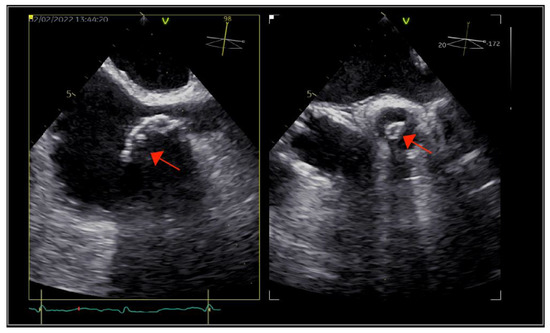

As part of the imaging assessment approach in IE, a thoracic, abdominal, pelvic, and cerebral computed tomography (CT) scan were conducted. The GCFS was visible in the SVC, but there was no evidence of vegetation at this level (Figure 3).

Figure 3. Cardiac computed tomography showing the calcified fibrin sheath in the superior vena cava (arrow), without evidence of vegetations.